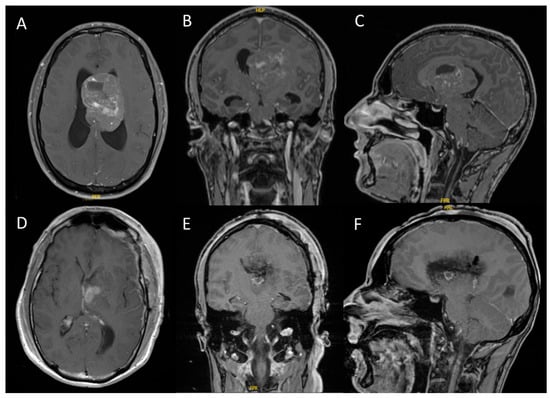

From January 2013 to December 2023, a total of 11 patients aged between 16 and 73 years with CN were treated at our center. The majority of tumors were located intraventricularly (n = 8), while the remaining three cases were situated in the pineal region, parietal lobe, and adjacent to the corpus callosum. Following the contrast-enhanced MRI evaluation (see Figure 1), gross total resection was achieved in eight cases, while the remaining three patients underwent subtotal resection. All microsurgical tumor resections were performed using either a transcallosal or transcortical approach with continuous electrophysiological monitoring and neuronavigation. Temporary external ventricular drainage was required in seven patients, and three patients ultimately required permanent ventricular shunting due to persistent hydrocephalus.

Figure 1. Intraventricular CN with hydrocephalus ((AC): preoperative T1-weighted MRI with gadolinium contrast; (DF): postoperative T1-weighted MRI with gadolinium contrast). These representative images are from case 1, a 31-year-old male who presented with headaches and cognitive deficits over the previous eight weeks. All tumors demonstrated contrast enhancement on MRI, with some cases exhibiting diffuse enhancement.